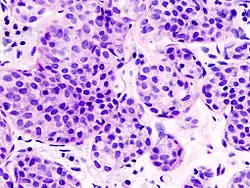

Pleomorphic | Classical-appearing but with pleomorphic cells. It may include signet-ring cells, or plasmacytoid cells (pictured) which have abundant cytoplasm and eccentric nuclei. | ![]() |